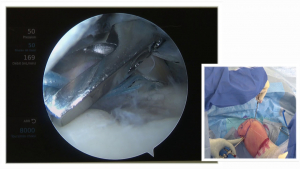

Workshop rééducation de l'épaule

Live surgery - Dr Steve Brenn

Vidéos

Tags:

brenn

épaule

live surgery

En savoir plus...